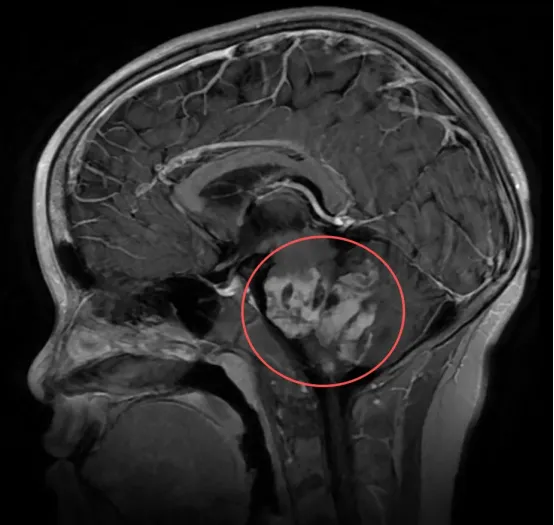

谢先生因头痛偶然发现桥脑占位性病变——桥脑作为脑干的一部分,手术风险极大。此时,他已出现间歇性头胀、偶发耳鸣及腿无力感,好在并没有明显的症状。找了多位医生,均建议保守观察,现阶段手术潜在风险太大,术后生活质量可能下降,因此不建议手术。面对正处上升期的事业、幸福的家庭,谢先生充满焦虑,下一步到底该如何做。恰逢巴教授来华,他获得了这次面对面交流机会。

巴教授分析指出,谢先生的头痛症状可能与当前脑内病灶并无直接关联。此类病例他在执业生涯中近十年遇到一例,谢先生是其近十年来接诊的第二位类似患者。

教授进一步提到,他曾接触过病情相似的国外案例。那些患者最终选择了开放性活检手术,术后均未出现新的神经功能障碍。活检组织被送至两到三个中心进行联合会诊,经综合评估后最终明确了病灶性质。只有获得确切的病理诊断,才能为后续治疗提供清晰方向。

关于为何不推荐穿刺活检,教授解释道:穿刺仅能获取极微量的组织样本(例如0.5毫米),如此小的样本量通常难以支撑全面、准确的病理分析。此外,穿刺过程存在出血等风险。因此,教授更建议通过开颅手术获取足量标本,为病理诊断提供可靠依据。

教授最后提出两条建议:一是继续保持临床观察;二是考虑通过手术方式进行活检,以获取足够病理组织明确诊断。他特别强调,在未明确诊断前,不应盲目进行化疗或放疗。